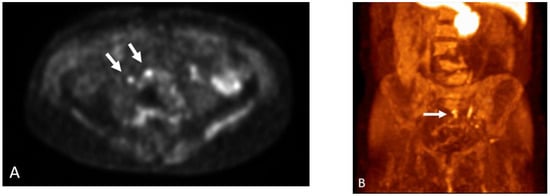

Detection of Loco-Regional Disease and Distant Metastases